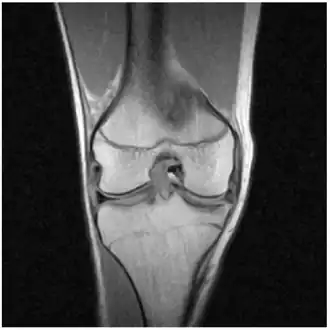

MRI of right knee revealing intra-articular and bucket-handle medial meniscus tear with the displaced fragment located in the intercondylar notch.

X-ray images (normally during weightbearing) can be obtained to rule out other conditions or to see if the patient also has osteoarthritis. The menisci themselves cannot be visualised with plain radiographs. If the diagnosis is not clear from the history and examination, the menisci can be imaged with magnetic resonance imaging (an MRI scan). This technique has replaced previous arthrography, which involved injecting contrast medium into the joint space. In straightforward cases, knee arthroscopy allows quick diagnosis and simultaneous treatment. Recent clinical data shows that MRI and clinical testing are comparable in sensitivity and specificity when looking for a meniscal tear.